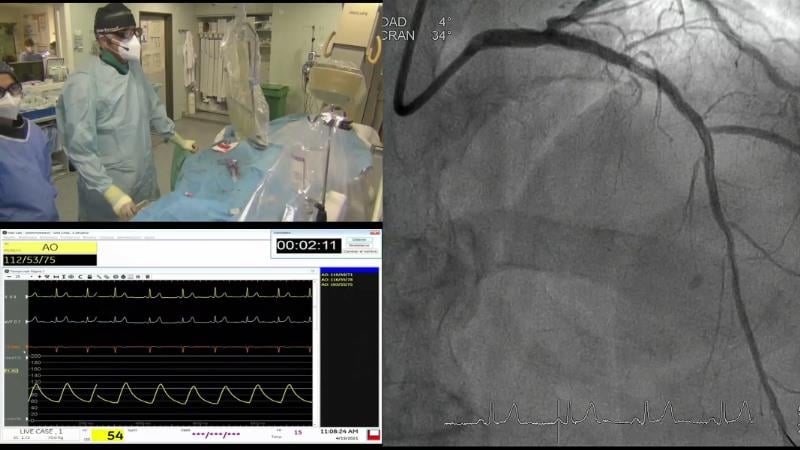

Follow the case study of this 70-year-old ex-smoker male patient with HTN, dyslipidemia, previous primary PCI to proximal and mid LAD because of anterolateral STEMI, presenting with syncope, and find out, through the debates around his treatment, how to use physiology in 2023.

- To learn how physiology pullbacks and angiography co-registration can help to define the patterns of atherosclerotic disease and guide treatment strategy

- To understand how to optimise PCI using physiology

- To learn key tips and tricks to obtain accurate physiological measurements